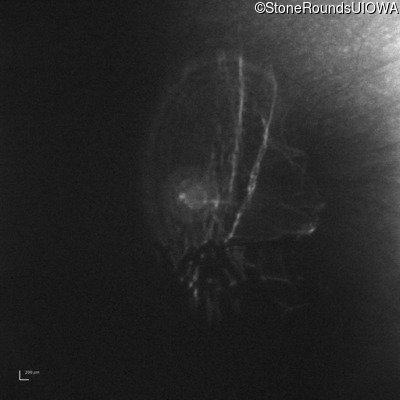

Infrared Fundus Photograph - Right - 10/300 sc

Exemplar

Infrared Fundus Photograph - Left - 10/350 sc